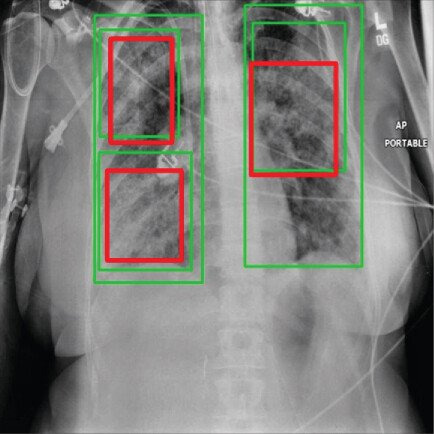

X-ray Analysis

Bone Fracture X-ray Analysis

Deep learning model for multi-class classification of pediatric bone fractures.

CNNMedical ImagingPyTorch